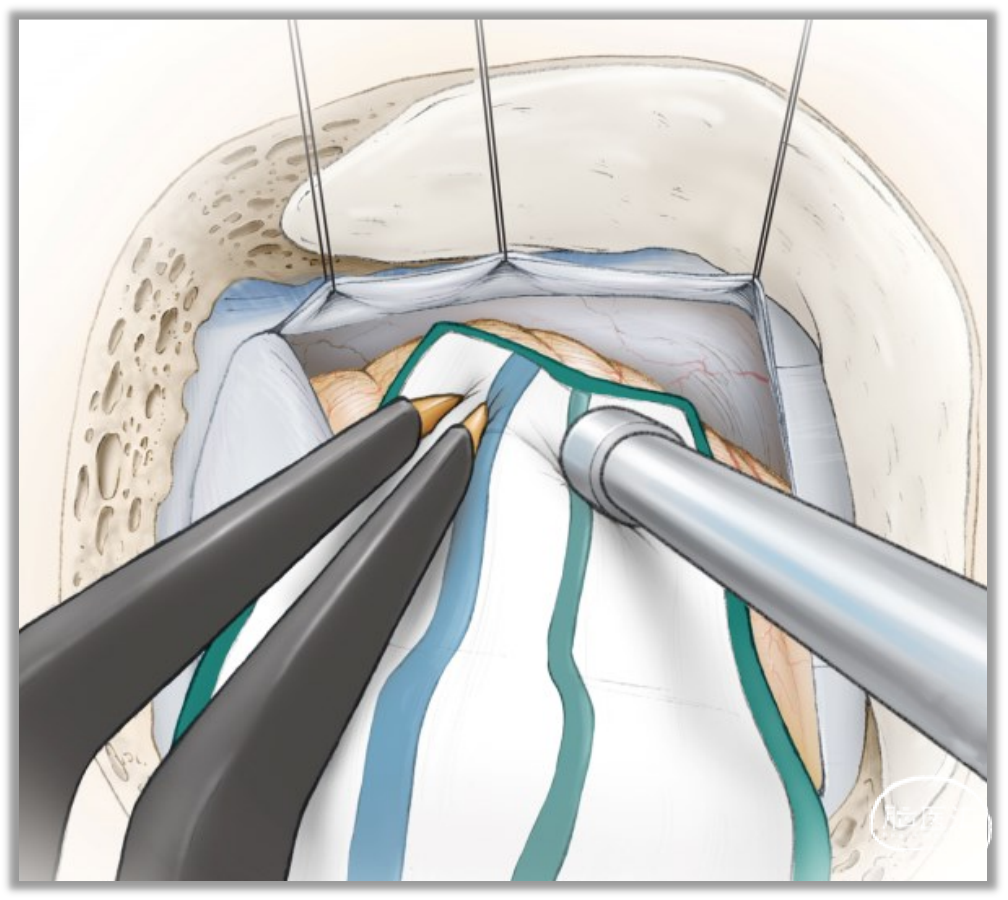

MVD术中应用神经内镜有助于责任血管的判断、评价神经根部减压情况及垫棉的大小和放置位置等。国内部分医院已开展全内镜MVD手术,笔者在此进行简要介绍(以右侧为例,开颅过程同前):

▼在小脑表面放置比脑棉稍大的橡胶手套,将脑棉沿手套表面进一步深入直至放置在后组颅神经附近,剪开小脑延髓外侧池蛛网膜,充分释放出脑脊液。

▼锐性分离,充分松解后组颅神经背侧的蛛网膜,并辨认出舌咽神经。继续锐性解剖绒球与听神经间的蛛网膜,蛛网膜必须充分松解,避免牵拉脑神经。

▼内镜下不需过多牵拉和剥离神经组织即能清晰地显露REZ区

▼用显微剥离子将责任血管充分游离后,将责任血管推移离开面神经出脑干区。

▼责任血管与面神经REZ区域用Teflon垫开。

▼必要时可用多块垫棉进一步推开血管以求减压充分。

内镜的局部放大和良好的照明能弥补手术显微镜管状视野的不足,不需过多牵拉和剥离神经组织即能清晰地显露REZ区并放置垫棉,对提高手术治疗效果、减少症状复发和并发症发生有一定临床意义,并使锁孔入路手术变得更加可行。